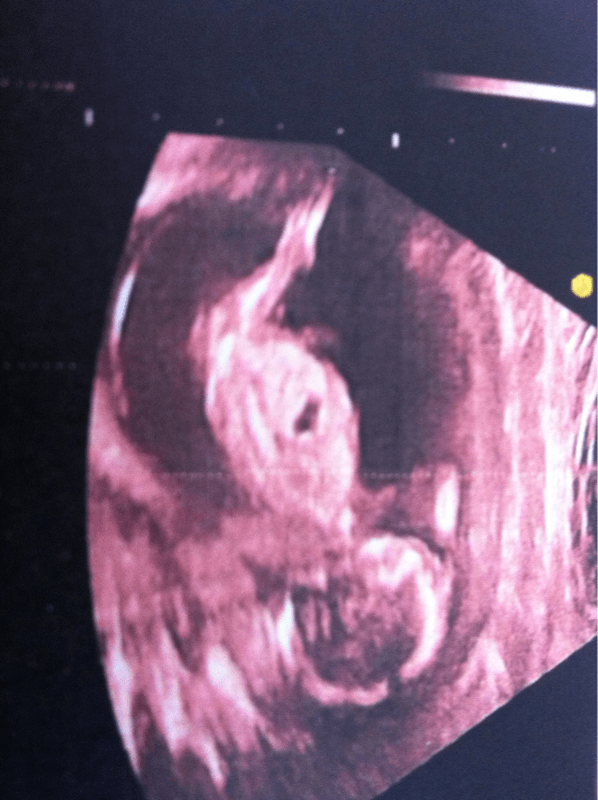

perri-ne voila ma fille a 9sa

Pièces jointes

• S6003882.JPG

S6003882.JPG

34.2 KB · Affichages: 153